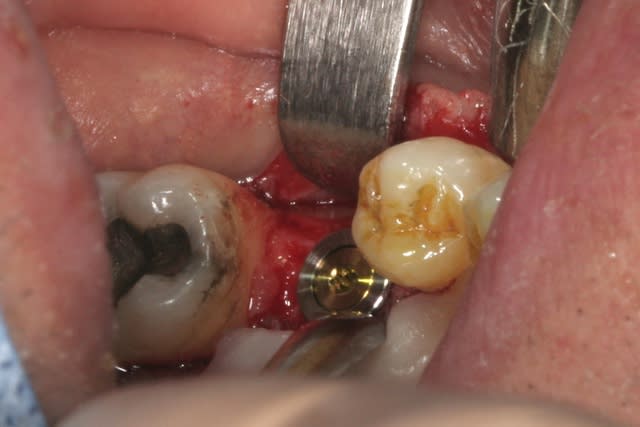

place aux photos!!!

forage, tout ce qu'il y a de plus classique pour ceux qui connaissent ID ou zimmer

pour un implant de 5mm de diamètre on s'arrête au foret de 4.4, passé ici sur 8mm au lieu des 11.5mm car j'étais dans du D3

l'interactive, (t'ain qu'il est beau!!!)

mise en place au CA qui bloque à 45Ncm...on est à 1 ou 2 mm de la crête....pas de problème, on retire le Fm (sympa, la vis, car il y a un filetage dans le Fm, ne risque plus de tomber!!!) et on se reprend direct dans le col de l'implant à la clef à cliquet...comme d'hab quoi...;-)

mise en place de la vis de cicat basse pour augmenter l'épaisseur de gencive attachée et on suture par dessus...si çà s'operculise, c'est pas grave en plus